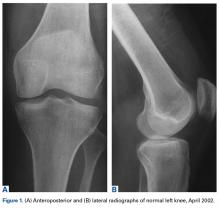

On initial referral to the department, in 2002, the patient, age 38 years at the time, had a 1-year history of progressive left knee stiffness and reduced range of motion (ROM). At the time, she recalled injuring the knee during an aerobics class 2 months prior. A physiotherapy trial (ROM actively and passively assessed 10°-90°) failed. All movement was painful, and 2 crutches were needed for ambulation. The patient was treated nonoperatively with analgesia and was advised to return to physiotherapy. Plain radiographs showed a small effusion but no bony abnormalities or fractures (Figures 1A, 1B).